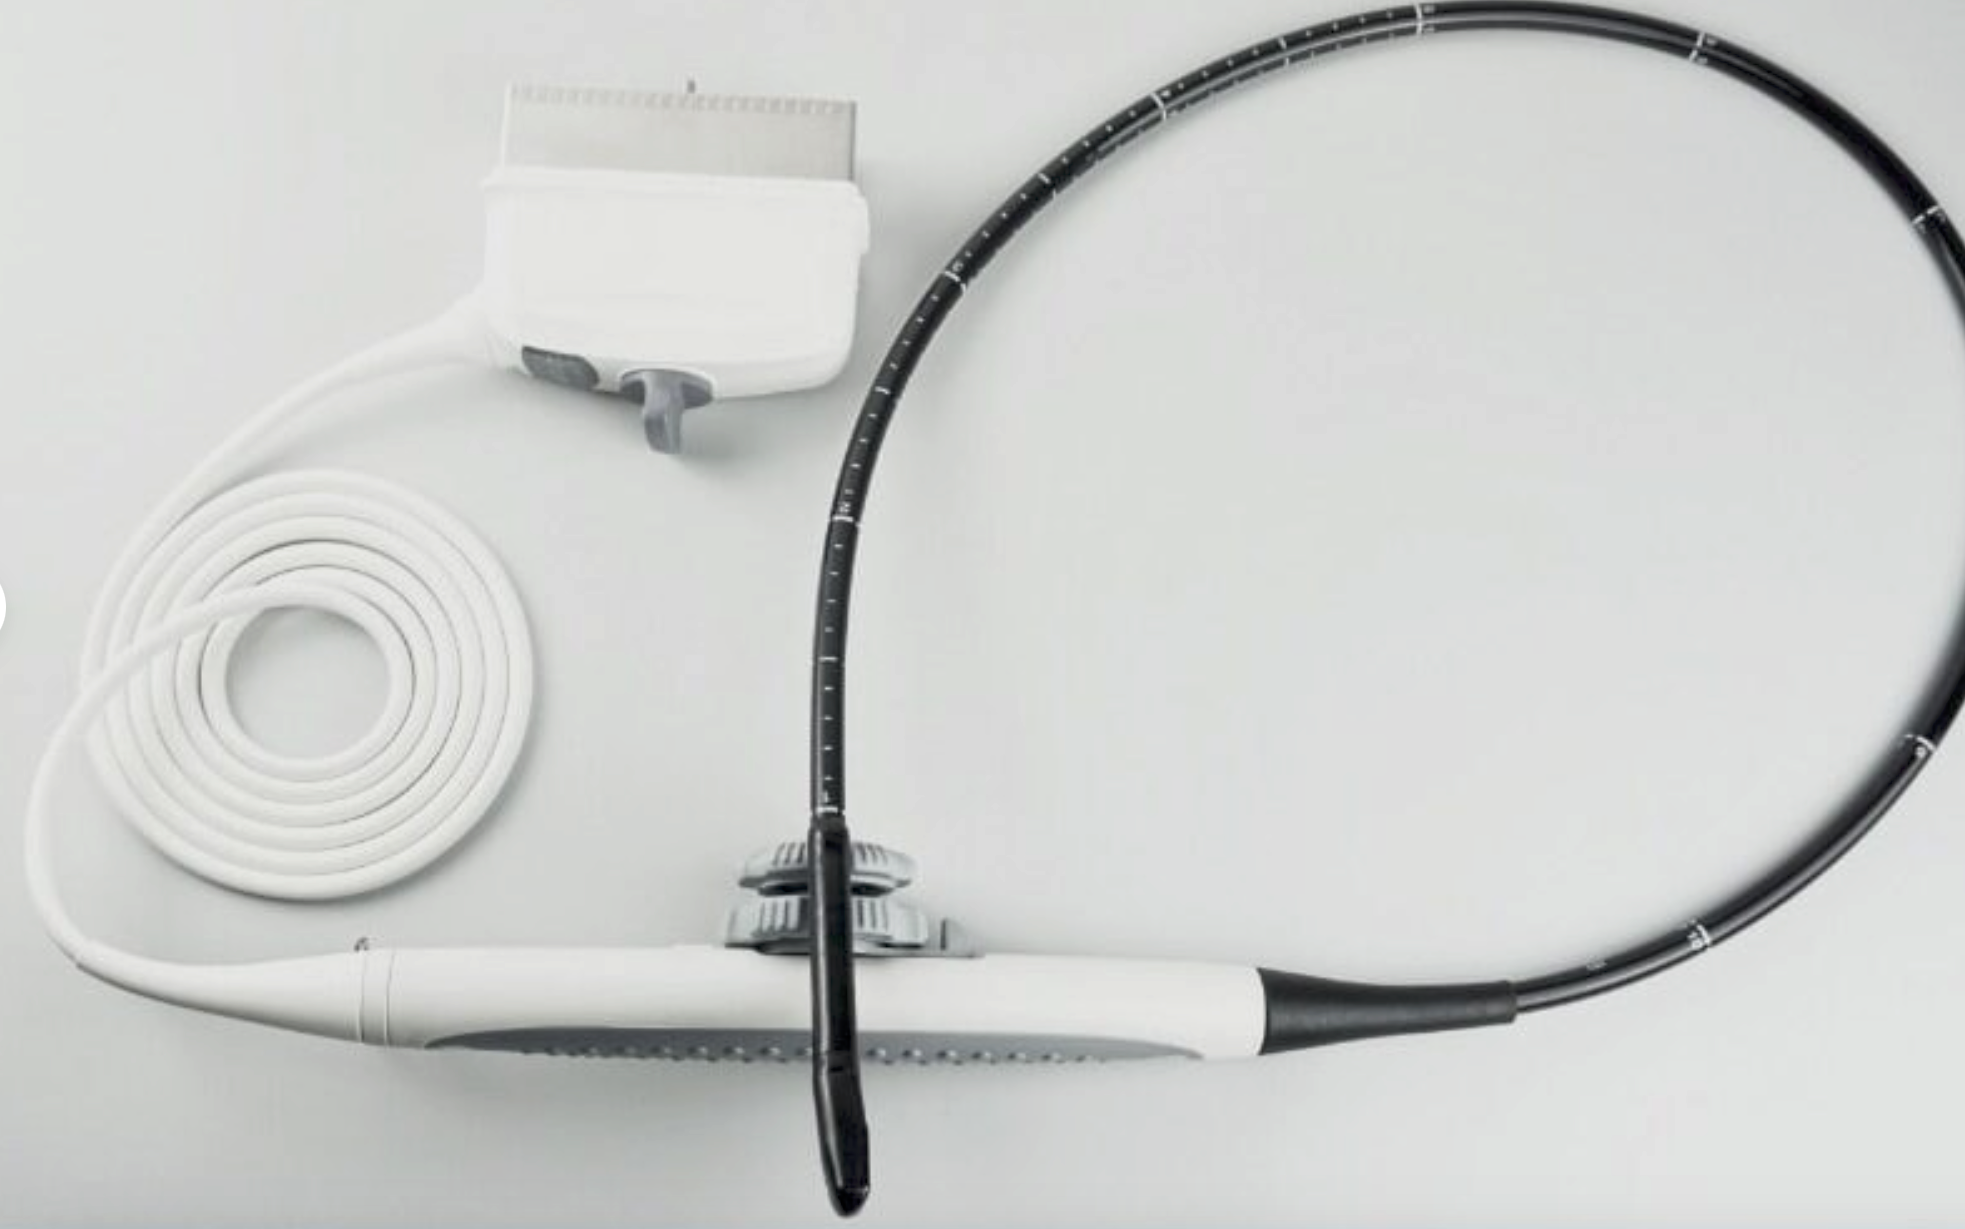

Model: RUS-6000A

Brand: Carejoy

![Digital 3D Ultrasound Scanner Convex + Linear 2Probe/Transducers +Oximeter [DHL] 190891435651 DIAGNOSTIC ULTRASOUND MACHINES FOR SALE](http://ultraultrasound.com/cdn/shop/products/s-l1600_55eda9f8-0657-42e5-b08f-fb450561b305.jpg?v=1571451481&width=562)

![Digital 3D Ultrasound Scanner Convex + Linear 2Probe/Transducers +Oximeter [DHL] 190891435651 DIAGNOSTIC ULTRASOUND MACHINES FOR SALE](http://ultraultrasound.com/cdn/shop/products/s-l1600_a77dd9e6-c605-475e-b3f1-9f86fc93dbb9.jpg?v=1571451481&width=800)

![Digital 3D Ultrasound Scanner Convex + Linear 2Probe/Transducers +Oximeter [DHL] 190891435651 DIAGNOSTIC ULTRASOUND MACHINES FOR SALE](http://ultraultrasound.com/cdn/shop/products/s-l1600_99c50fa2-36fe-4a5b-bcf7-6ee7a0bac49b.jpg?v=1571451481&width=800)

![Digital 3D Ultrasound Scanner Convex + Linear 2Probe/Transducers +Oximeter [DHL] 190891435651 DIAGNOSTIC ULTRASOUND MACHINES FOR SALE](http://ultraultrasound.com/cdn/shop/products/s-l1600_d50ffb69-35d9-4e4d-a2f5-fd83f8b897dc.jpg?v=1571451481&width=500)

![Digital 3D Ultrasound Scanner Convex + Linear 2Probe/Transducers +Oximeter [DHL] 190891435651 DIAGNOSTIC ULTRASOUND MACHINES FOR SALE](http://ultraultrasound.com/cdn/shop/products/s-l1600_e2646f33-3bdd-4c03-a93f-5ecff438ba60.jpg?v=1571451481&width=500)

![Digital 3D Ultrasound Scanner Convex + Linear 2Probe/Transducers +Oximeter [DHL] 190891435651 DIAGNOSTIC ULTRASOUND MACHINES FOR SALE](http://ultraultrasound.com/cdn/shop/products/s-l1600_73c5e27c-235b-4093-a5c8-da4c1fd871e6.jpg?v=1571451481&width=500)

![Digital 3D Ultrasound Scanner Convex + Linear 2Probe/Transducers +Oximeter [DHL] 190891435651 DIAGNOSTIC ULTRASOUND MACHINES FOR SALE](http://ultraultrasound.com/cdn/shop/products/s-l1600_65d7ce40-ffb2-4c36-b75e-a0711be5b0e9.jpg?v=1571451481&width=800)

![Digital 3D Ultrasound Scanner Convex + Linear 2Probe/Transducers +Oximeter [DHL] 190891435651 DIAGNOSTIC ULTRASOUND MACHINES FOR SALE](http://ultraultrasound.com/cdn/shop/products/s-l1600_76b8761b-3e35-42b3-8ef6-77d9bb2d1b38.jpg?v=1571451481&width=800)

![Digital 3D Ultrasound Scanner Convex + Linear 2Probe/Transducers +Oximeter [DHL] 190891435651 DIAGNOSTIC ULTRASOUND MACHINES FOR SALE](http://ultraultrasound.com/cdn/shop/products/s-l1600_cfe20fc7-5697-4c1a-8391-2580b856e6e0.jpg?v=1571451481&width=787)

![Digital 3D Ultrasound Scanner Convex + Linear 2Probe/Transducers +Oximeter [DHL] 190891435651 DIAGNOSTIC ULTRASOUND MACHINES FOR SALE](http://ultraultrasound.com/cdn/shop/products/s-l1600_358e66eb-4359-4c64-b1e8-a9dcd0e814ad.jpg?v=1571451481&width=787)

![Digital 3D Ultrasound Scanner Convex + Linear 2Probe/Transducers +Oximeter [DHL] 190891435651 DIAGNOSTIC ULTRASOUND MACHINES FOR SALE](http://ultraultrasound.com/cdn/shop/products/s-l1600_30e9b73a-963b-405f-aac6-1e35df6dd5a5.jpg?v=1571451481&width=500)

![Digital 3D Ultrasound Scanner Convex + Linear 2Probe/Transducers +Oximeter [DHL] 190891435651 DIAGNOSTIC ULTRASOUND MACHINES FOR SALE](http://ultraultrasound.com/cdn/shop/products/s-l1600_5f5dd2f5-1278-4642-992d-76ca0ab3df32.jpg?v=1571451481&width=800)